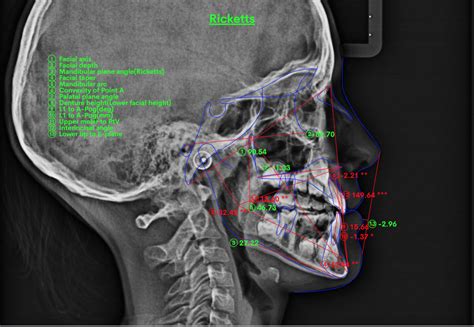

Como el plano oclusal es relativamente más bajo de lo normal, los individuos con EMV presentan una exposición gingival excesiva con un labio inferior que cubre los bordes incisales de los caninos y los premolares superiores. Estos hallazgos clínicos pueden conducir al clínico al diagnostico de EMV, lo que debe confirmarse con una cefalometría. En un grupo que presentaba sonrisa gingival se encontró que la distancia entre el plano palatino y el borde incisal de los incisivos superiores (altura facial anterior) era aproximadamente 2 mm más alta que la de individuos que no presentaban sonrisa gingival.

Análisis cefalométrico. La altura maxilar anterior se mide entre el plano palatino y el borde incisal de los incisivos superiores.